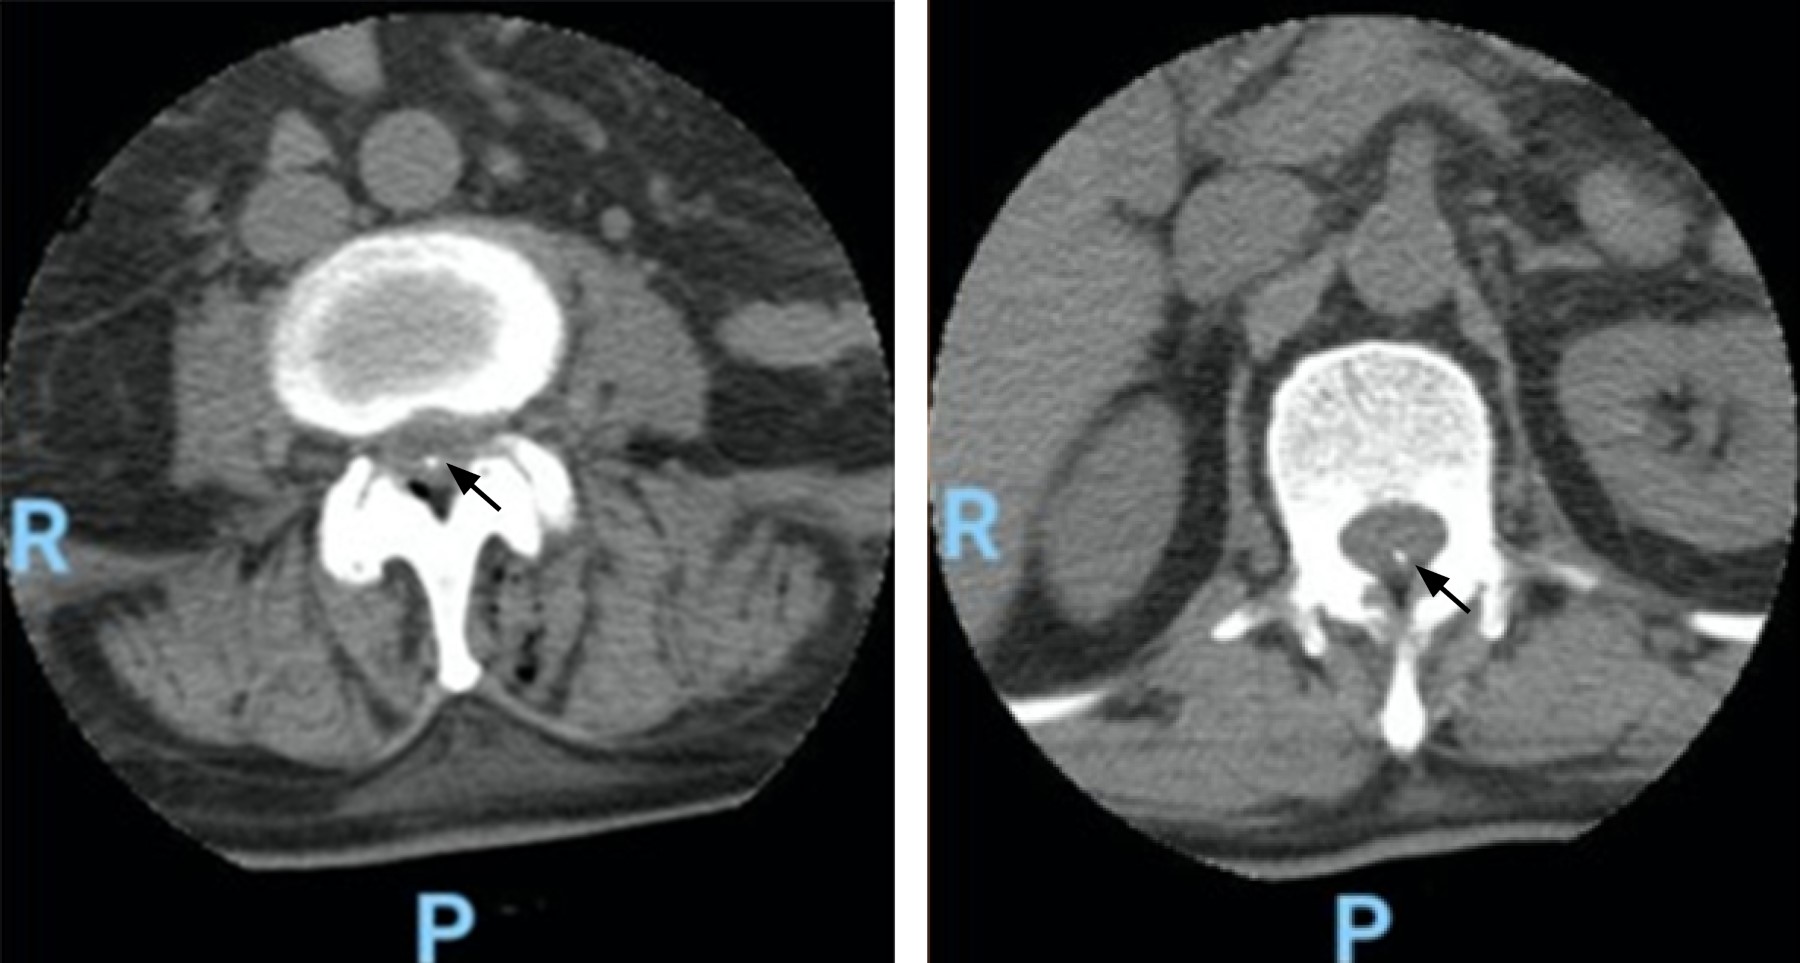

Type of catheter removal and epidural catheter connection